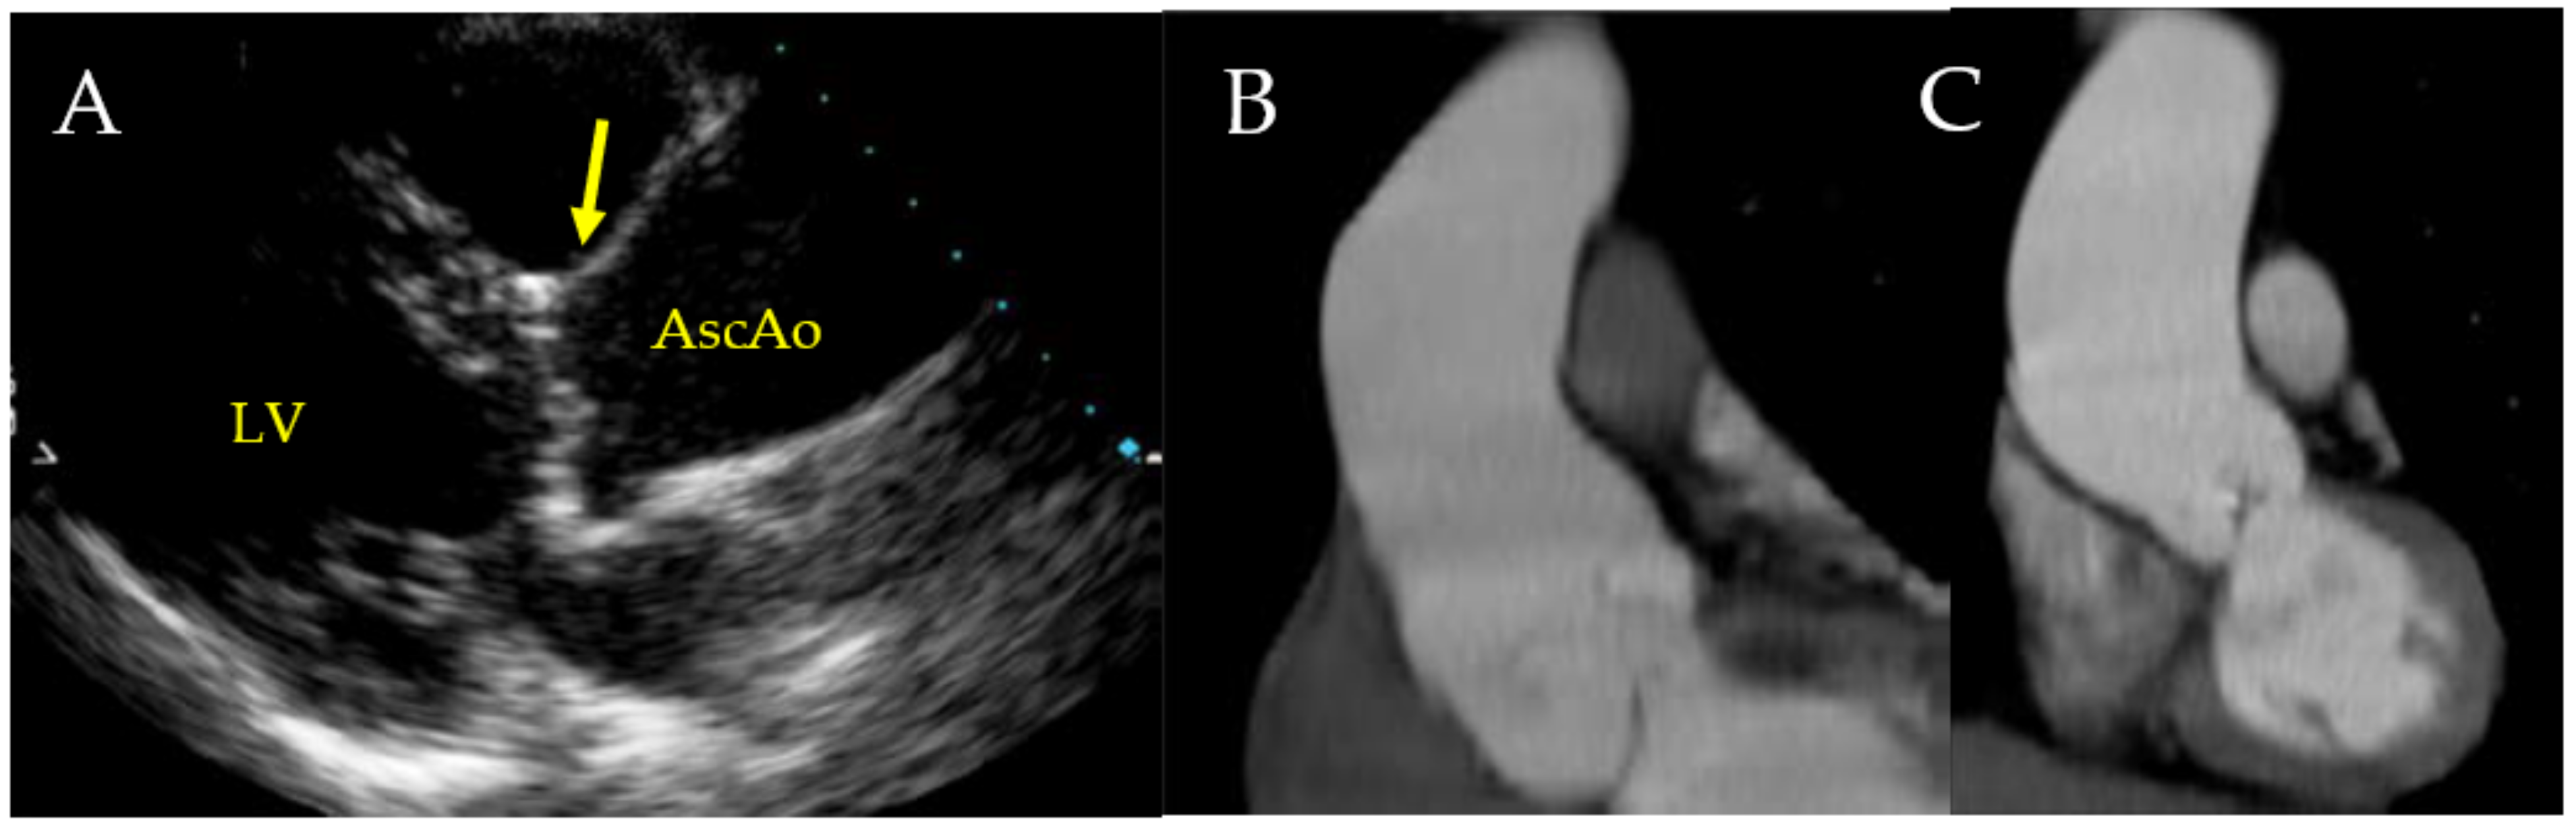

TTE determines the morphology of the valve, the connected hemorheology, the anatomical features of the root system, the diameter and the wall alteration of ascending aorta, and conditions like the aortic coarctation associated with BAV. In aortic root determination, TTE allows for measuring the sinotubular junction (STJ), especially in some aortopathy related to BAV (Figure 6).

Figure 6.

TTE shows enlargement of the sinotubular junction related to R-L cusp fusion.

An early diagnosis of bicuspid aortopathy is likely offered by the use of TTE [42,105,106,107,108]. Although TTE is substantially a method for assessing the morphology of the aortic root and proximal ascending aorta, it is known that the correct visualization of the mid-distal portion of ascending aorta and the arch may present some difficulty in adults. In these cases, both computed tomographic (CT) and MR investigation may be offered a better visualization with a global evaluation of the ascending aorta. In patients who have contraindications to CT or MR, a TTE is suitable for reaching the diagnosis [43,105,109,110]. Likewise, in scheduling serial surveillance, it is more convenient to use MR than CT since it avoids extensive radiation exposure. (Figure 11)

Figure 11.

(A–C). Depicts representative findings on echocardiography and computed tomography (CT). In (A), the transthoracic echocardiogram shows normal dimensions of the sinuses of Valsalva (arrow) and a dilated ascending aorta. Ascending aorta denotes proximal ascending aorta, and LV denotes left ventricle. In (B,C), the CT images reveal dilatation of the aortic root and dilatation of the ascending aorta and proximal arch, respectively. Licenses Centre Cardiologique du Nord; order date 27 July 2022; order number 5357160571198; publication NEJM; Title: Aortic Dilatation in Patients with Bicuspid Aortic Valve.